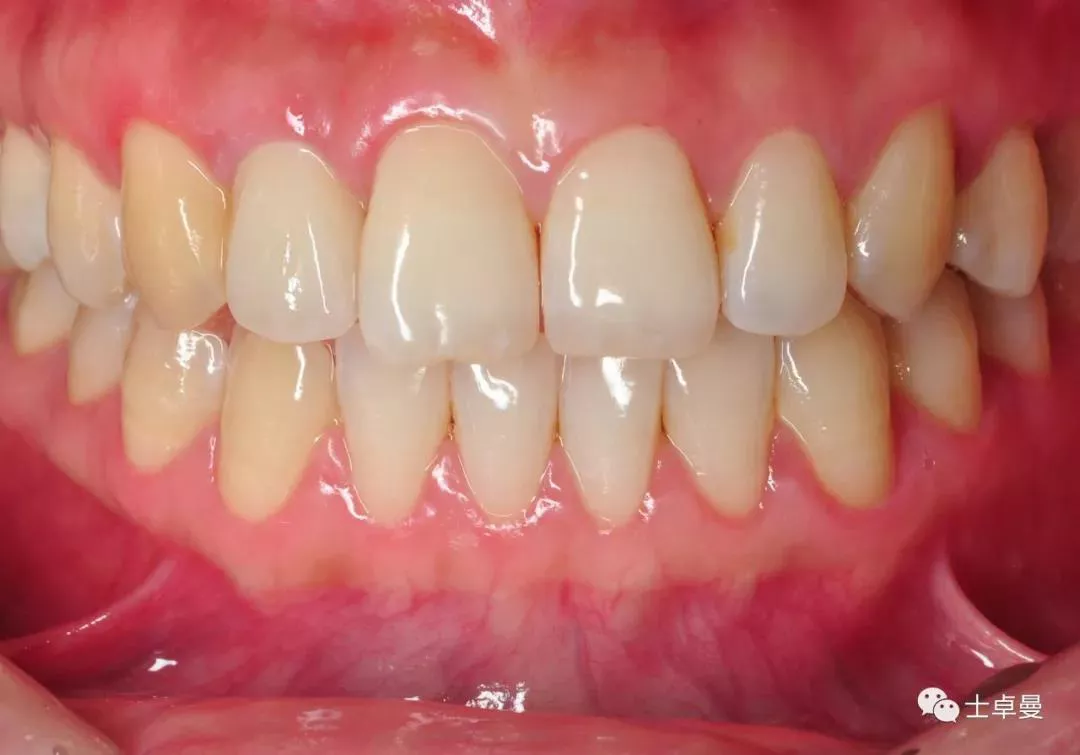

口内完成修复当日

完成修复一年后复查

修复后3年复查

患者微笑照